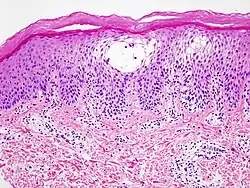

Coupe histopathologique d'une dermatite spongieuse (cliniquement : dermatite dyshidrosique)